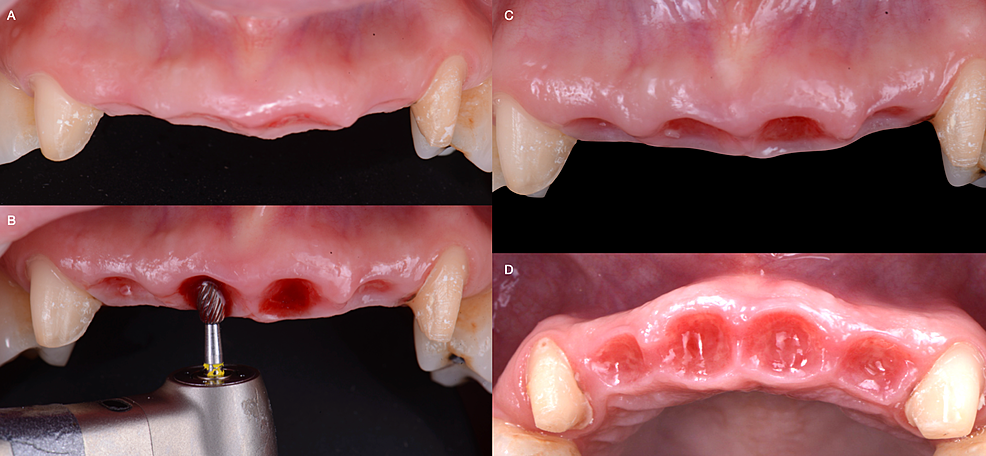

A milled provisional restoration was fabricated based on pre diagnostic wax-up of the patient. The maxillary canines were prepared, and the patient was sent for teeth extractions. The maxillary central and lateral incisors were extracted. Particulate cortico-cancellous allograft bone (Cortical/Cancellous Chips, AlloSource Headquarters, Centennial, CO, USA) with collagen dressing (Puracol, Collagen Wound Dressing, Medline Industries Inc, Northfield, IL, USA) and resorbable sutures (Polysyn FA, Surgical Specialties Corporation, Wyomissing, PA, USA) was placed to achieve complete socket seal (Figures 3A, 3B). The milled provisional restorations, made of polymethyl methacrylate, were cemented with an ovate pontic shape in the extraction sites without interfering with the sutures. (Figure 3C) The initial provisional restorations applied light pressure and included a space between the soft tissue and the provisional restoration, enabling the patient to clean underneath the pontic and connector areas.

The patient returned two weeks later, and the provisional restorations were removed. The pontic units were built-up using self-curing acrylic resin (Jet Tooth Shade, Lang Dental, Wheeling, IL, USA) to establish contact under slight pressure and maintain the developed ovate soft tissue contour. The interproximal areas between the pontic units were opened with a disc (Acrylic Temporization System, Brasseler USA Dental, Savannah, GA. USA) to provide space for the papilla tissue. The patient again returned two weeks later, and the same procedure was performed.

The patient was seen again for follow-up two months later, and the same procedure was performed. The thickness of the soft tissue was measured with a periodontal probe. (Williams Color-coded single end probe, Hu-Friedy Mfg. Co., LLC. Chicago, IL, USA) Fortunately, there was adequate keratinized tissue along with the maxillary labial site of the anterior teeth region. Carbide and diamond football burs (Medium Football bur, Brasseler USA Dental, Savannah, GA, USA) were used to improve the architecture of the pontic sites and prevent black triangles (Figures 4A, 4B). The provisional restoration was built-up again using acrylic resin material (Acrylic Temporization System, Brasseler USA Dental, Savannah, GA, USA) to match the contour provided by the football burs (Figure 4B, 4C). Two weeks later, the provisional restorations were removed to evaluate the final contour of the soft tissue (Figure 5).